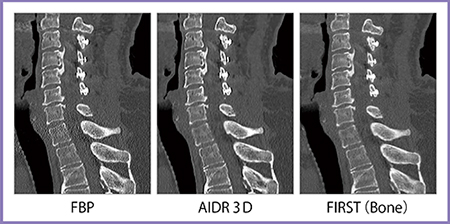

股関節CTは,FBPと比べるとAIDR 3Dでも大幅にノイズが低減されているが,FIRSTではさらにノイズが低減され,骨梁構造も描出できている(図7)。また,ストリークアーチファクトが強く出やすい肩口の頸椎CTでも,FIRSTではアーチファクトが抑制できている(図8)。

図7 股関節CT

図8 頸椎CT